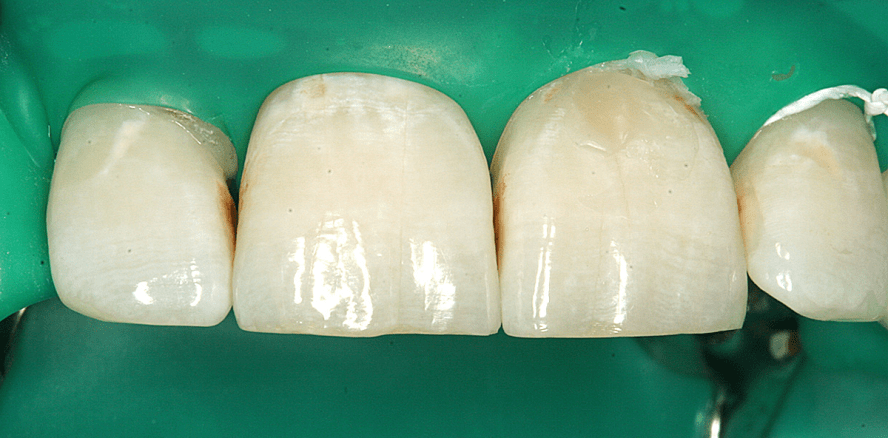

Die praktische Anwendung soll abschließend an mehreren klinischen Beispielen veranschaulicht werden. Im Patientenfall 2 (Abb. 3–6) wurde die Behandlung im Jahr 2010 durchgeführt. Es handelte sich um eine Raucherin (zehn Zigaretten täglich) mit einer unzureichenden Mundhygiene und einem hohen Zuckerkonsum. Die Patientin hatte sich einige Jahre zuvor einer festsitzenden kieferorthopädischen Behandlung unterzogen. In der Ausgangssituation existieren (Abb. 3) zervikale White Spots an den Zähnen 12–22, bräunliche Verfärbungen und Nikotinablagerungen und eine invasiv behandlungsbedürftige kariöse Läsion an Zahn 21. Die Zähne wurden gereinigt, es erfolgte eine absolute Trockenlegung (Abb. 4–5), in Regio 21 wurde eine Compositefüllung gelegt und die Zähne 12–23 wurden per Infiltration (Icon®, DMG) laut Herstellerangaben behandelt. Die Abbildung 6 zeigt das Ergebnis direkt nach der Infiltrationsbehandlung. Die Patientin beklagte keine Nebenwirkungen bzw. Überempfindlichkeiten. Bei ihr wird seither regelmäßig (alle sechs bis neun Monate) ein professionelles Biofilmmanagement inklusive einer Fluoridierung durchgeführt.